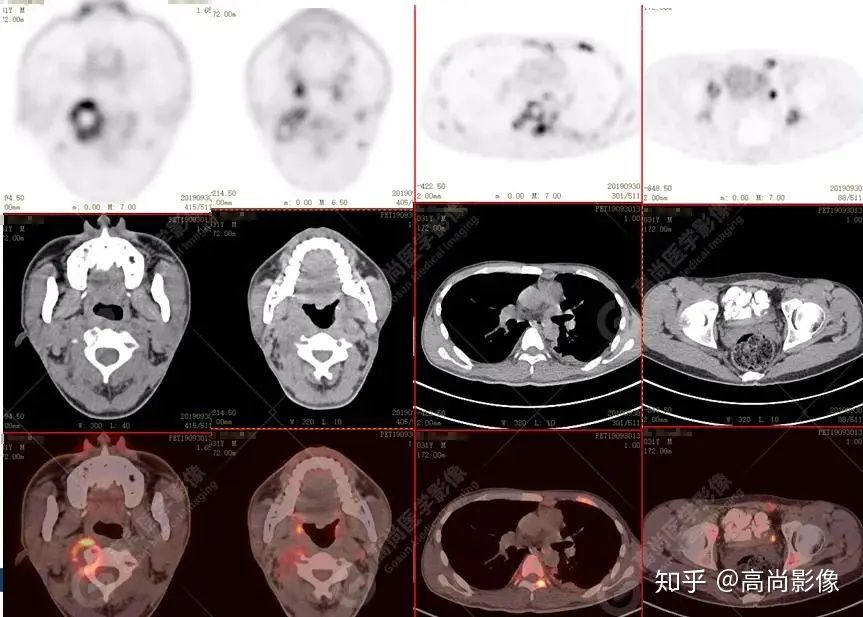

脊柱多發(fā)椎體及附件骨質(zhì)破壞,代謝不均性增高

全身多發(fā)高代謝腫大淋巴結(jié),中央代謝缺損

【PET/CT提示】雙肺、左側(cè)胸膜多發(fā)結(jié)節(jié)影,全身多處骨質(zhì)破壞,全身多發(fā)淋巴結(jié)腫大,代謝攝取不均勻性增高。

2.全身多系統(tǒng)、多形態(tài)、多發(fā)病灶(肺部、胸膜、淋巴結(jié)、骨),18F-FDG攝取不均性增高;

特征:肺部病灶簇狀分布,上葉尖段及下葉背段為著;腫大淋巴結(jié)分布不對稱,無融合、中央有壞死改變,與淋巴瘤、轉(zhuǎn)移瘤等有一定的鑒別診斷意義;

診斷意見:綜合考慮感染性病變(結(jié)核),建議相關(guān)實(shí)驗(yàn)室檢查。